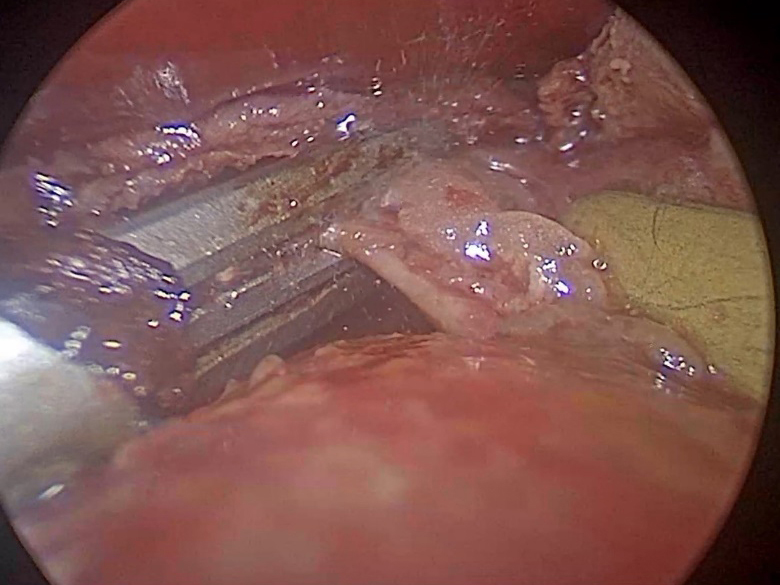

術中の様子。

術中のカメラ映像。超音波凝固切開装置を用いて心膜を処理しているすぐ下に動く心臓がある。